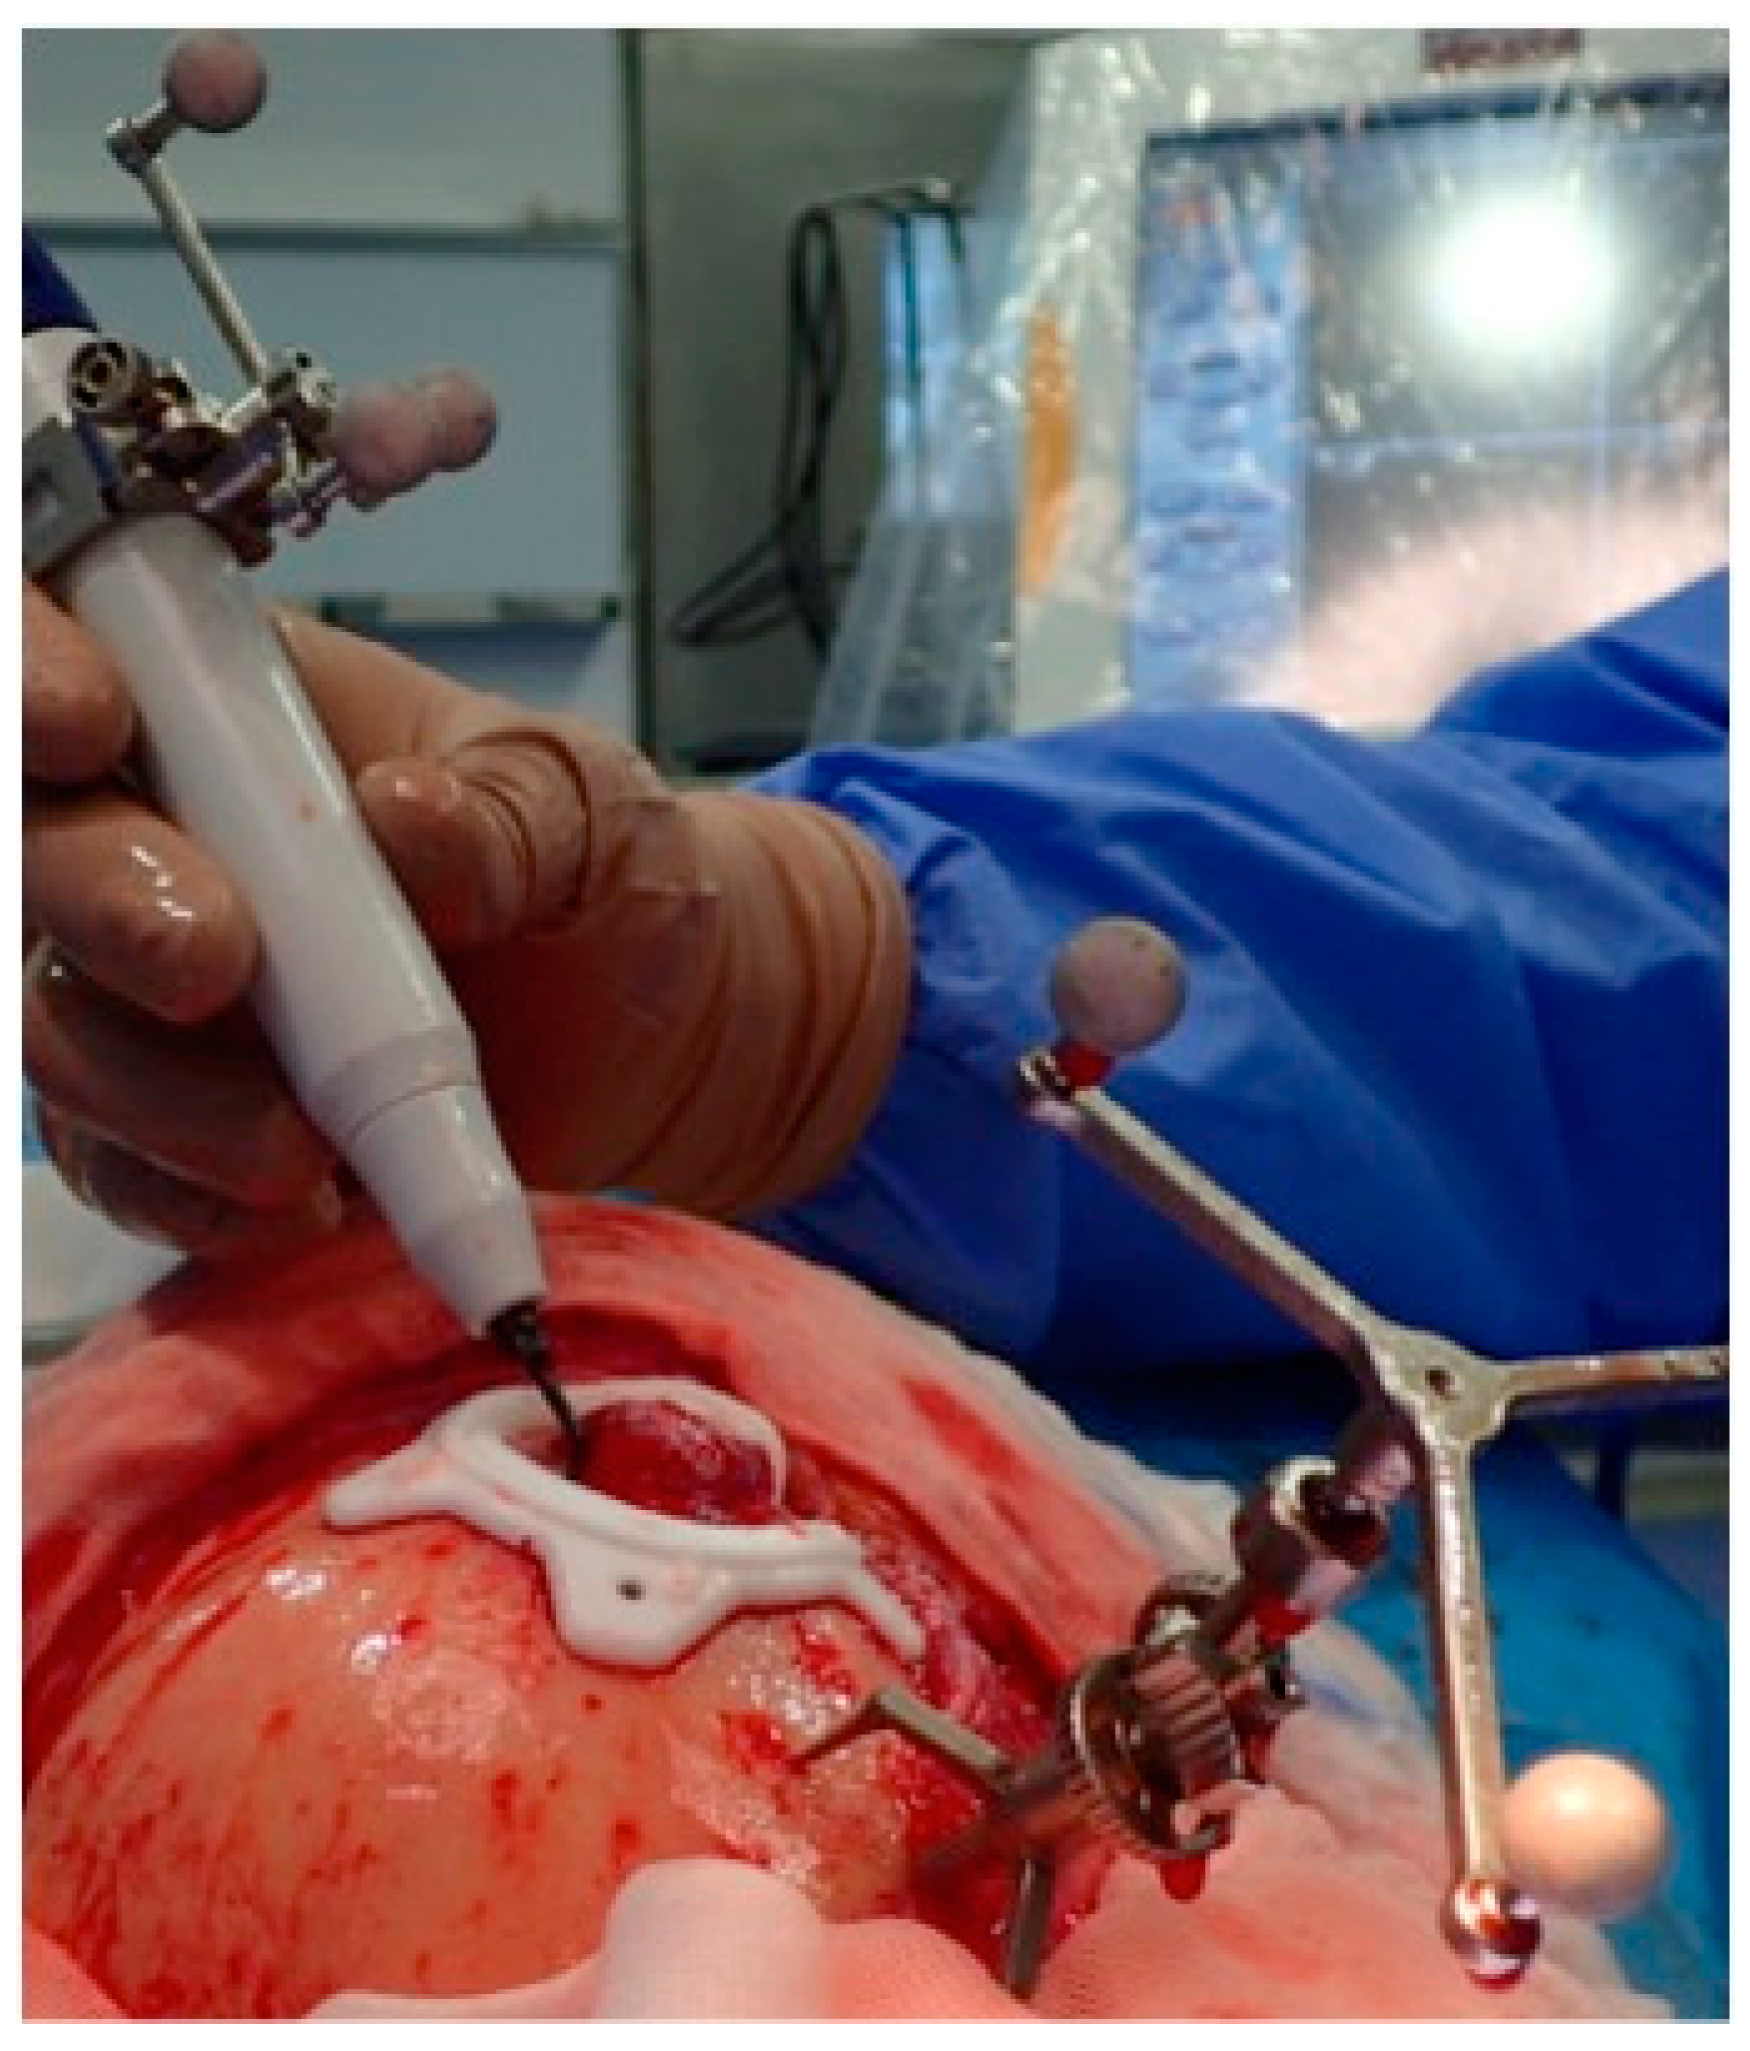

2.3.3. Surgical Navigation

- Dean, A.; Heredero, S.; Solivera, J.; Sanjuan, A.; Alamillos, F.J. Computer-assisted and navigated piezoelectric surgery: A new technology to improve precision and surgical safety in craniomaxillofacial surgery. Laryngoscope Investig. Otolaryngol. 2022, 7, 684–691. [Google Scholar] [CrossRef]